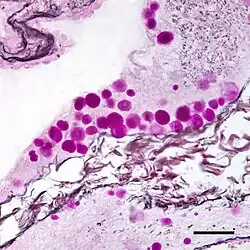

Histology of a multilayered corpus amylaceous of the prostate.